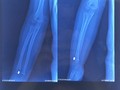

Cùng có bệnh lý về cổ bàn chân như bà M., một bệnh nhân nam 35 tuổi bị đau cổ chân dai dẳng sau chấn thương do chơi đá bóng. Kết quả chụp cộng hưởng từ cho thấy bệnh nhân bịtổn thương viêm xương sụn bóc tách xương sên ở cổ chân - loại tổn thương hiếm gặp. Bệnh nhân đã được phẫu thuật ghép xương sụn nguyên khối (lấy xương sụn từ khớp gối để ghép), điều trị tổn thương. Sau mổ, tình trạng đau của bệnh nhân khi vận động mạnh dần được cải thiện và bệnh nhân có thể trở lại sinh hoạt bình thường sau 3 tháng.